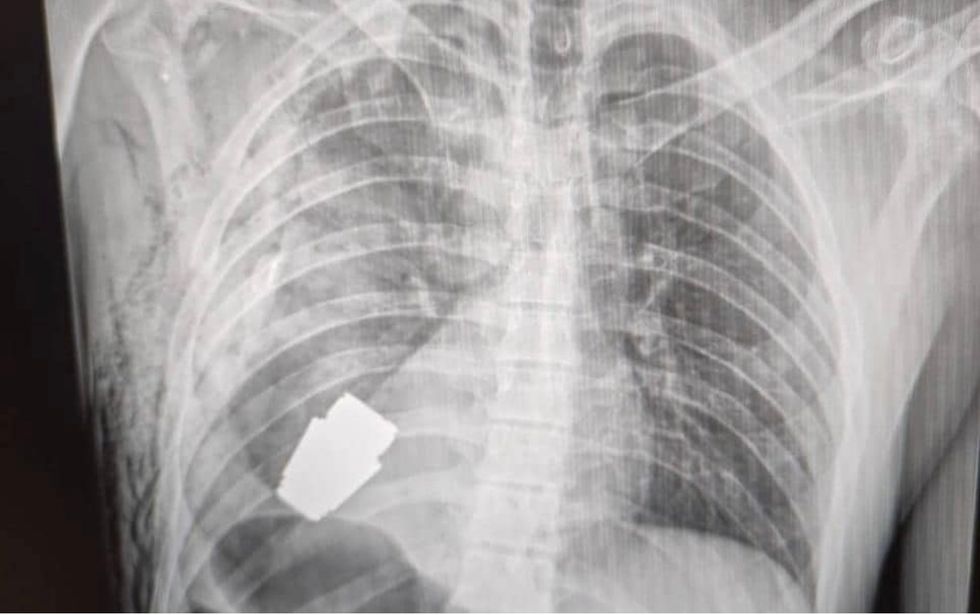

Images shared on social media showed the X-ray picture taken of the grenade as well as the surgeon posing with the grenade after a successful surgery.

A Ukrainian soldier had to have an unexploded grenade surgically removed after it was lodged in his torso. | Facebook

The soldier was engaged in combat when the grenade was fired from a launcher and went into his torso but did not explode

The grenade was fired from a launcher attacked to an assault rifle during combat between Ukrainian and Russian troops in Bakhmut, Donetsk.